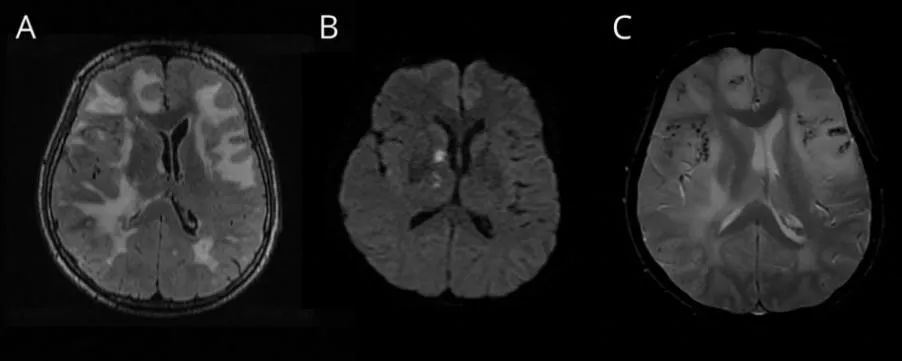

【影像】淀粉样脑血管病的影像诊断与鉴别诊断

淀粉样脑血管病

淀粉样变性脑血管病的影像诊断